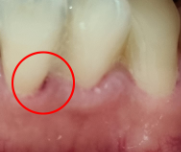

오늘 치과 가서 아래쪽 부분 스케일링(?) 받고, 집에 와서 거울 보니 상처가 있는데 괞찬나요?아니면 연고 같은거 발라 주어야 될까요?

스켈링을 하는 과정중에 생긴거는 시간이 지나면 자연스럽게 아물기 떄문에 약을 따로 바르거나 하지는 않으셔도 됩니다.

특별히 연고를 발라주지 않아도 시간이 지나면 아물기에 그냥 두어도 됩니다.